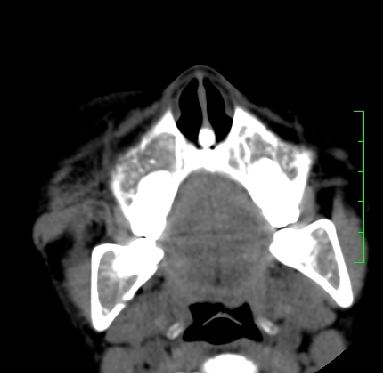

标题: PED1889:上颌窦病变

m,10y,外伤做ct

支持;骨纤,有皮肤色素沉着,性早熟时为albright综合征。

霉菌性鼻窦炎

骨化性纤维瘤可能性大。(与骨纤的鉴别:常见于面颅骨,多骨发病)